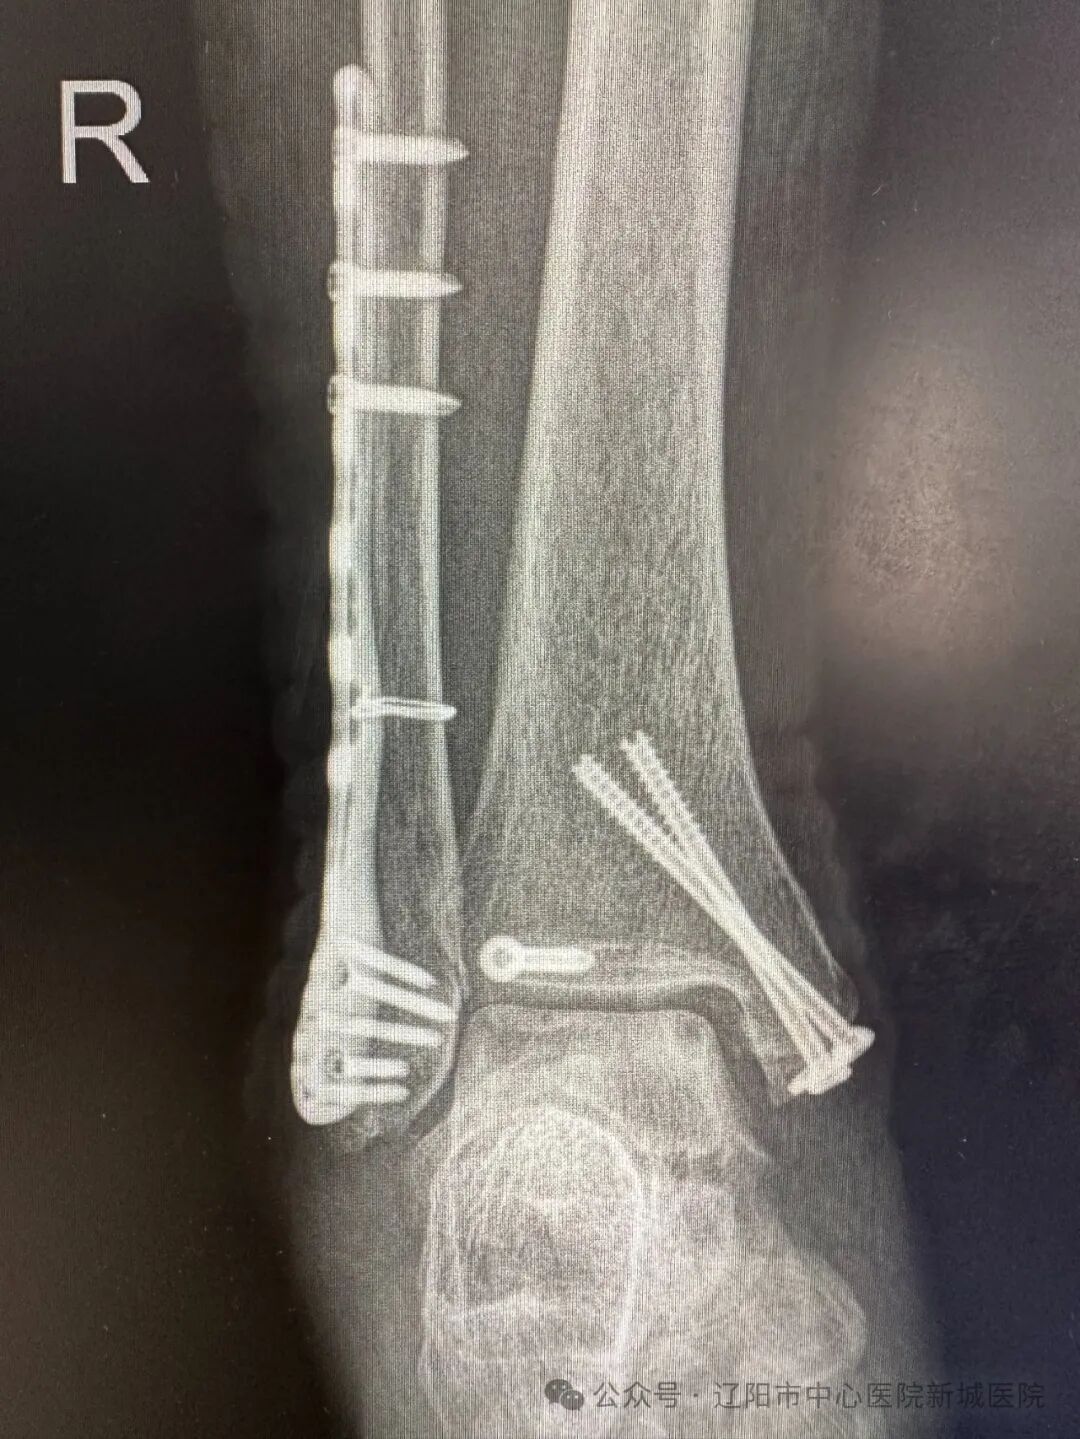

在完成術(shù)前準(zhǔn)備后,按照擬定了手術(shù)計劃,姚醫(yī)生與團(tuán)隊醫(yī)生們?yōu)楸∨渴┬辛?ldquo;踝關(guān)節(jié)骨折切開復(fù)位內(nèi)固定術(shù)”。術(shù)中所見骨折位置和預(yù)判一致,三踝骨折。在C型臂X線機的輔助下,完成了外踝固定、后踝固定、內(nèi)踝固定,螺釘和鋼板位置固定穩(wěn)固,一次復(fù)位成功,手術(shù)順利完成。

術(shù)后經(jīng)過醫(yī)務(wù)人員的精心護(hù)理,薄女士手術(shù)切口恢復(fù)良好。她出院后,按照醫(yī)囑,積極進(jìn)行康復(fù)訓(xùn)練,恢復(fù)了踝關(guān)節(jié)正常的屈伸負(fù)重活動,未出現(xiàn)創(chuàng)傷性踝關(guān)節(jié)炎?;謴?fù)正常生活的薄女士逢人便說:是新城醫(yī)院的醫(yī)生治好了我的踝關(guān)節(jié)骨折,讓我又能高高興興跳廣場舞了!